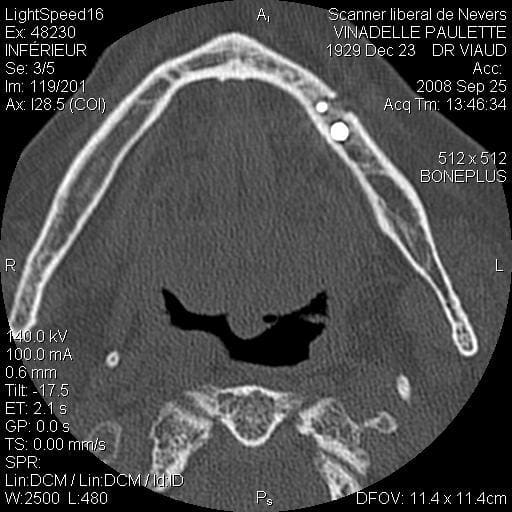

Je suis désolé mais le seul problème que j’ai eu sur un maxillaire inférieure (celui que j’ai mis en photo d’ailleurs) c’est une rupture de la table interne en 33 34 (suite à un mouvement inopportun de la patiente, ce que j’aurais du prévoir) j’ai repris le cas 3 mois plus tard et no problème.

scan te montrant la façon dont je contourne les obstacles